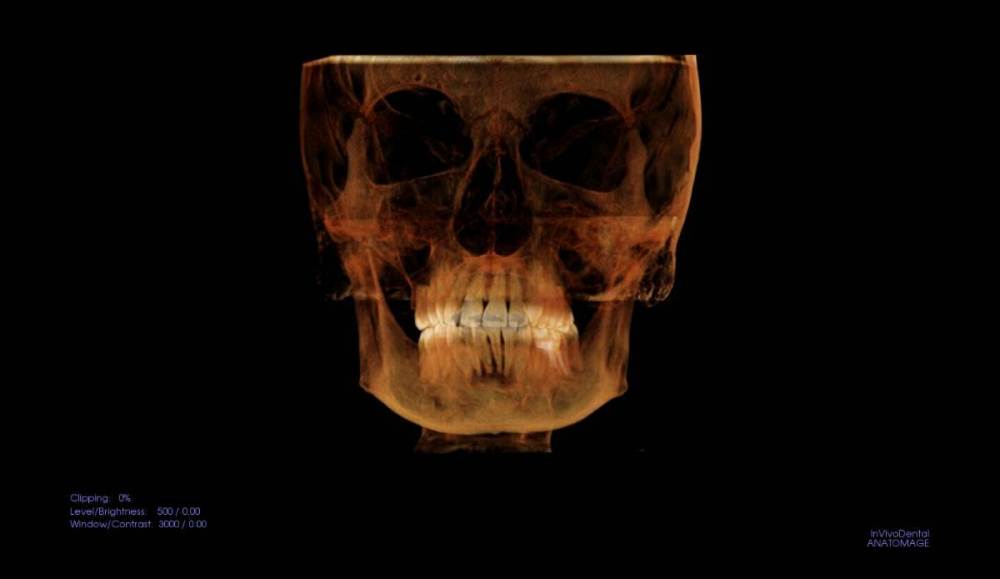

Ситуация в следующем: у меня стоят брекеты, пока только на верхней челюсти, ношу ~8 мес. На нижней челюсти в переднем отделе обнаружена цементно-костная дисплазия. Делалось два КТ, первое в 2021 (перед установкой верхней челюсти), второе месяц назад для оценки динамики перед установкой брекетов на низ. Дисплазия стала немного больше, но выглядит лучше (больше костной ткани).

Вопрос: можно ли ставить брекеты на нижнюю челюсть при таком диагнозе? Какие есть риски, осложнения? На фото КТ, сделанное в 2021